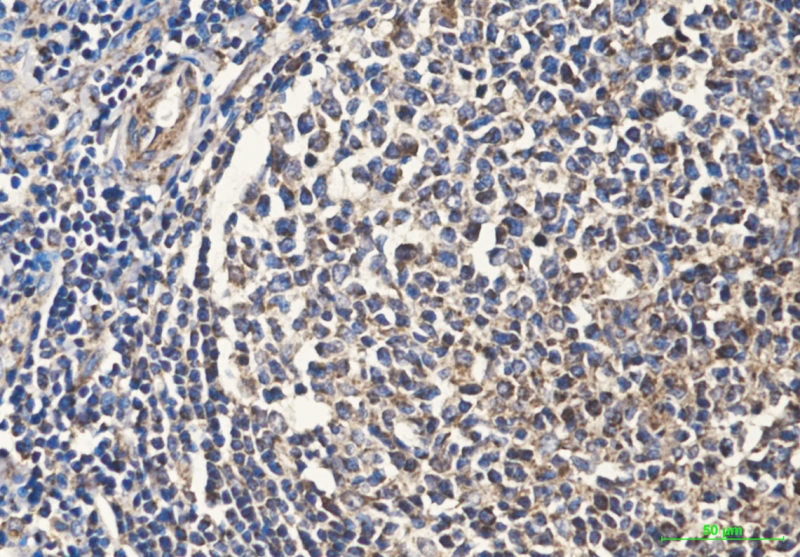

Mouse Monoclonal CD45 Antibody

中文名:CD45抗体

Catalog:IPDX20769

Size: 50μl / 100μl

Application: WB IF IHC ICC FCM Elisa

Reactivity:Human,Mouse,Rat

Synonyms:GP180; L CA; CD45 antigen

Type:Primary antibody